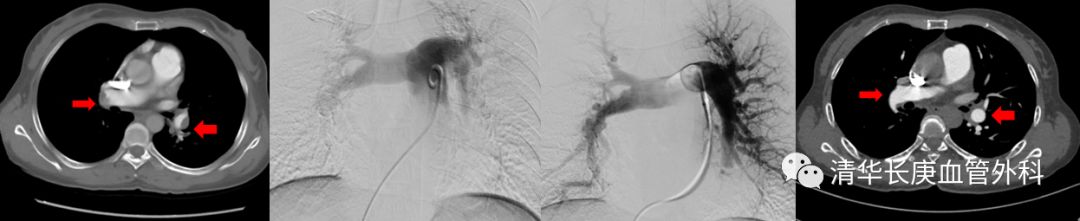

患者张某,女性,49岁,反复发作胸痛、憋气症状3年,1年前再次急性发作,就诊我院血管外科,诊断为肺栓塞、慢性血栓栓塞性肺动脉高压,肺动脉压力高达96mmHg。考虑患者复发肺动脉栓塞可能,经微创肺动脉栓塞腔内溶栓治疗后症状缓解,肺动脉压力降至70mmHg左右。此后患者坚持药物治疗,但仍有活动后喘憋等症状,近1年肺动脉压力逐渐升高至70-80mmHg,间断发作右心衰竭,最严重时6min步行距离只有不够100m,严重影响日常生活,时刻危及患者生命。

(术前双侧肺动脉主干内血栓,术中溶栓后改善,术后复查主干血栓消失)